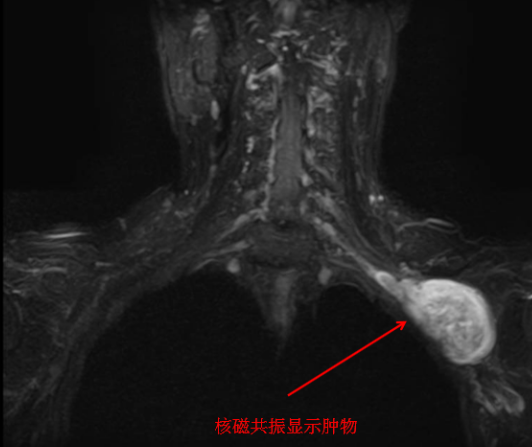

听了刘大爷的诉求,陈主任先安排他进行相关检查,从体格检查、超声及磁共振结果来看,考虑刘大爷左侧锁骨下肿物的性质为神经源性肿瘤——神经鞘瘤的可能性大。

刘大爷住院后,考虑到手术如果采取切断锁骨的方式,会对锁骨的损伤非常大,陈步国主任组织科内人员进行术前讨论,分析手术中可能存在的困难及风险,制定出另一套损伤小、恢复快的方案——不切断锁骨,直接采取“锁骨上、下联合切口”,通过锁骨上、下切口于锁骨下做通道取出肿物手术方案。次日,手术按时进行,术中探查见肿物与臂丛神经相连,上肢的一些主要的动、静脉都在肿物的下方。手术风险性非常大,稍有不慎,就会损伤血管造成大出血的状况。术中按照术前拟定的手术方案,采取锁骨上、下切口,通过锁骨下隧道方式仔细剥离肿物上神经束,这就要求主刀医生具有丰富的手术经验和过硬的显微外科技术。经过3个半小时的努力,手术顺利完成。取出的肿物经过测量,大小在7cm×5cm×5cm,竟然比一个鸡蛋还要大。肿物取出后用术中肌电图生理检测臂丛神经呈现正常电生理表现,手术过程中很好地保护了臂丛神经。术后肿物送病理检查再次明确诊断为神经鞘瘤。